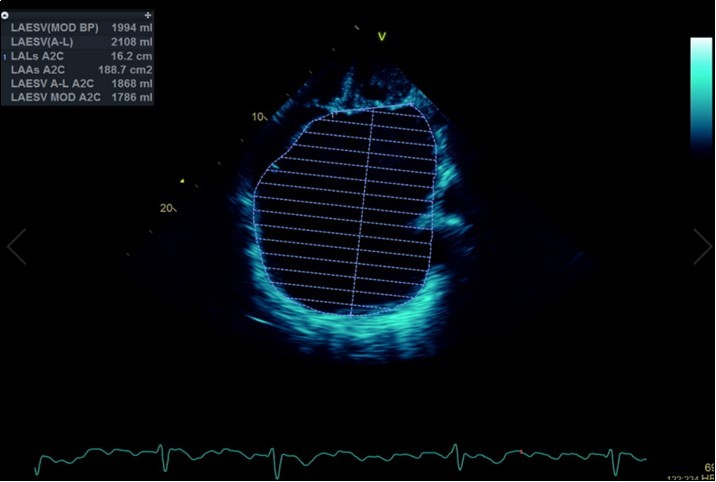

A dramatically dilated left atrium was seen on a TTE (see Figure 2a, Figure 2b, Figure 2c, and Figure 2d). Severe mitral stenosis with associated regurgitation was evident, with a mean gradient across the valve of 11mmHg and a hyperdynamic left ventricle. The left atrial volume measured by Simpson’s biplane method (see Figure 2c) was 2108mL, or 1548.5 ml/m2, based on height 1.55 metres and weight 44 Kg. Normal left atrial volume in a woman is 16 - 34 ml/m21. The computed tomography scan (CT) chest AP view (see Figure 3) is also shown.

Figure 2d.Transthoracic echocardiogram Apical 2C view. Left atrial size estimation by Simpson’s biplane method from apical 2C view. Severely enlarged left atrium (estimated 2108ml, 1548.5ml/m2)